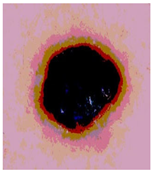

![]() | ![]() | ![]() | ![]() |

| Img1 | --- Pixel Intensity (0–255) ---> | ||

| Img2 | --- Pixel Intensity (0–255) ---> | ||

| Img3 | --- Pixel Intensity (0–255) ---> | ||

| Img4 | --- Pixel Intensity (0–255) ---> | ||

| Img5 | --- Pixel Intensity (0–255) ---> | ||

| Img6 | --- Pixel Intensity (0–255) ---> | ||

| Img7 | --- Pixel Intensity (0–255) ---> | ||

| Img8 | --- Pixel Intensity (0–255) ---> | ||

| Img9 | --- Pixel Intensity (0–255) ---> | ||

| Img10 | --- Pixel Intensity (0–255) ---> | ||